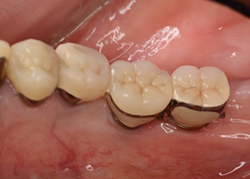

先日インプラント治療が終わった患者さんはインプラント手術時、遊離歯肉移植術(FGG)を併用しました。

インプラントの被せ物の周囲に角化歯肉もあり、お掃除しやすい形態になっています。治療後もメインテンスしやすいでしょう。